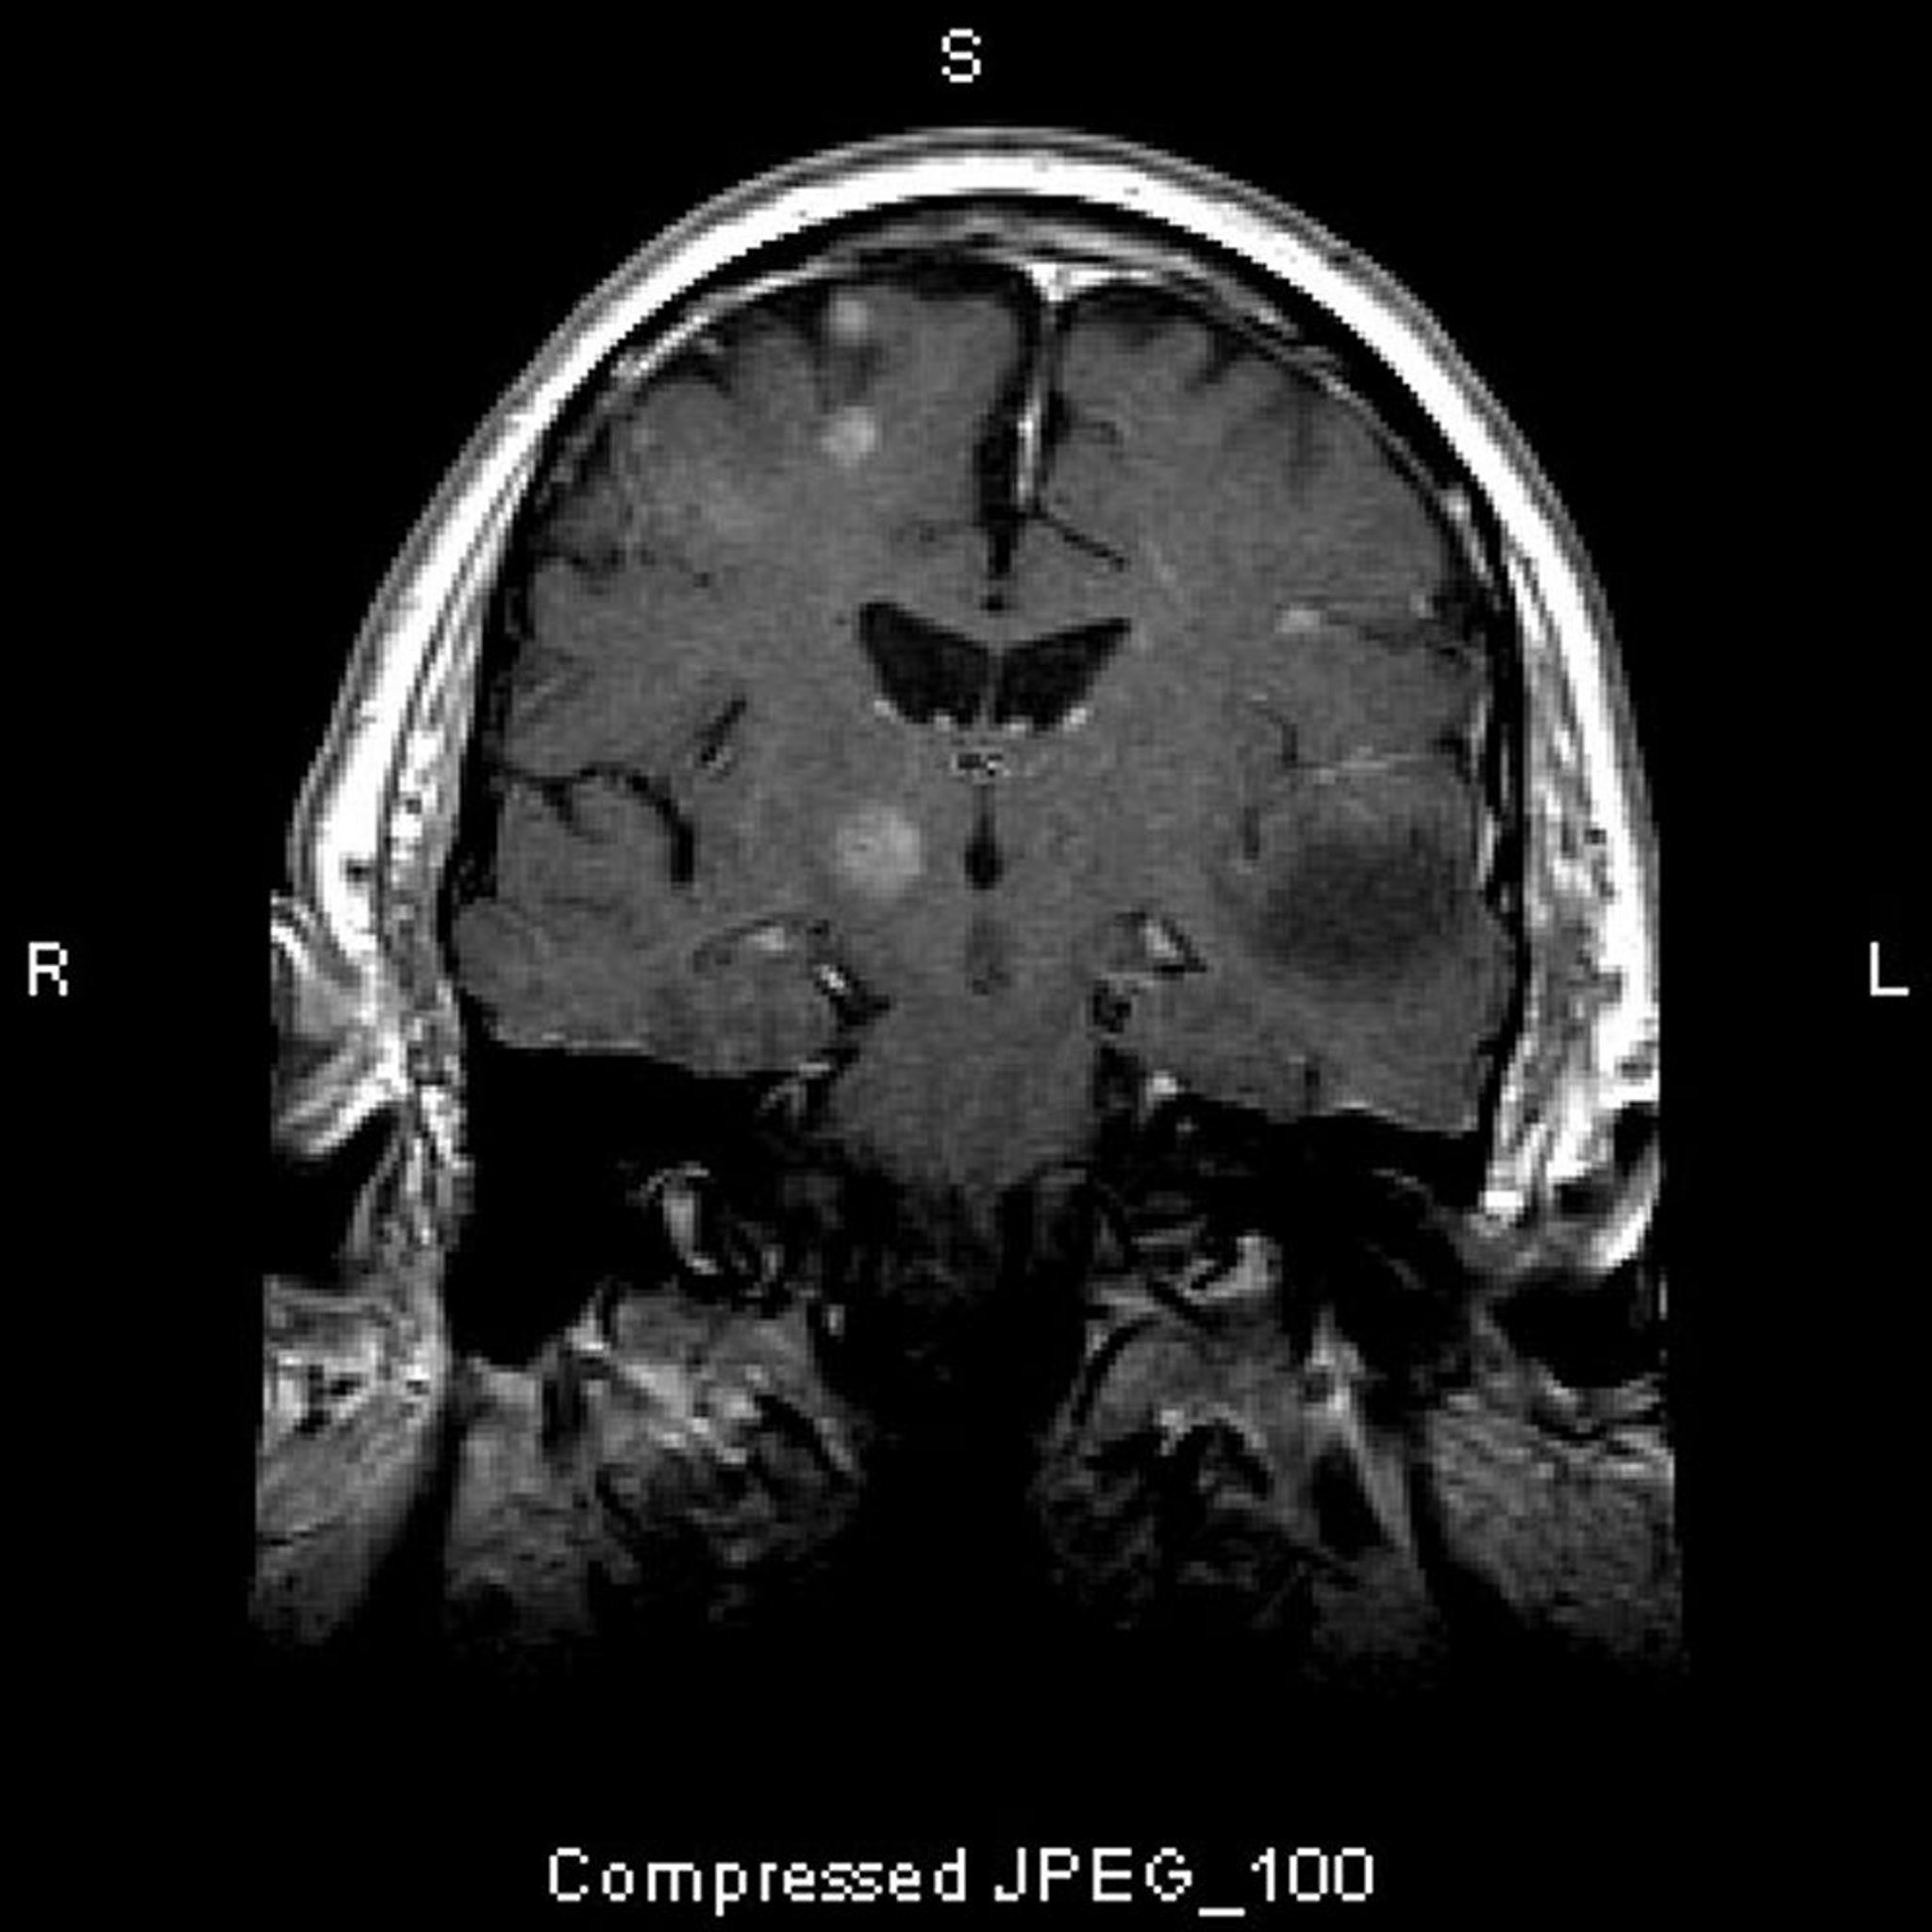

Metástases no cérebro

Essa RM mostra múltiplas lesões encefálicas, representando tumores metastáticos. Mais de 80% das metástases cerebrais são múltiplas.

Imagem cedida por cortesia de William R. Shapiro, MD.